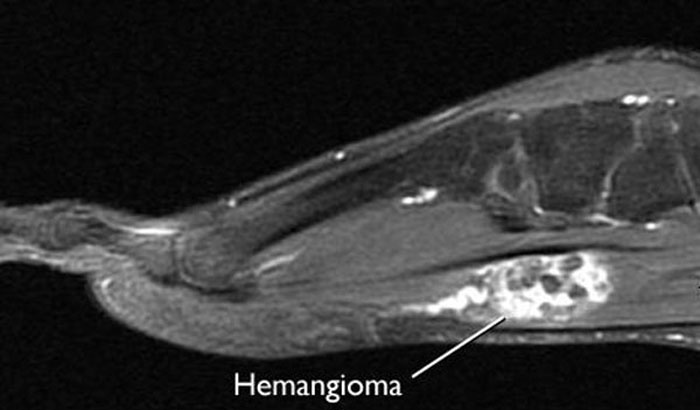

Magnetic resonance imaging (MRI) scans. MRI scans can create clear images of soft structures like a hemangioma. Hemangiomas in an MRI scan are often described as a "bag of worms" due to the way the blood vessels pack around one another.

MRI of hemangioma

This MRI scan shows a hemangioma in the sole of the patient's foot.